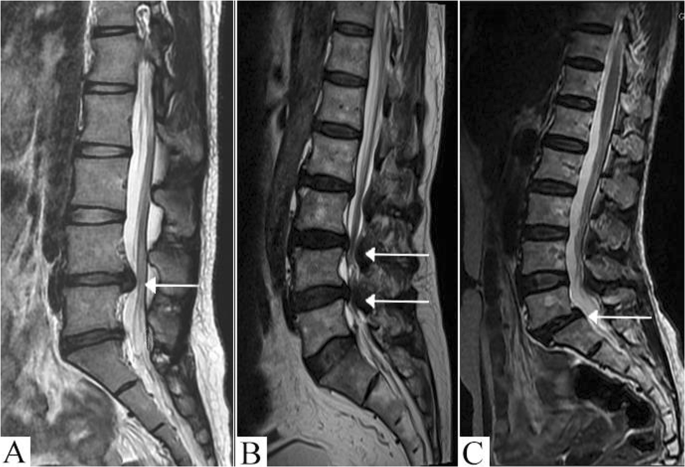

Diagnosis of Herniated Discs

Diagnosing a herniated disc typically involves a combination of physical examinations, imaging tests, and patient history. Healthcare providers will often begin with a comprehensive physical exam, assessing the range of motion, reflexes, and areas of tenderness. Following this, imaging techniques such as X-rays, MRIs, or CT scans may be utilized to visualize the spine and identify any disc protrusions. In some cases, doctors may also use electromyography (EMG) to assess nerve function. Research indicates that MRIs are particularly effective in diagnosing herniated discs, with an accuracy rate of over 90%. It’s important to understand that while imaging can pinpoint the presence of a herniated disc, it does not always correlate with the severity of symptoms. Many individuals with herniated discs lead active lives without requiring surgical intervention, emphasizing the need for a personalized approach to diagnosis and treatment.